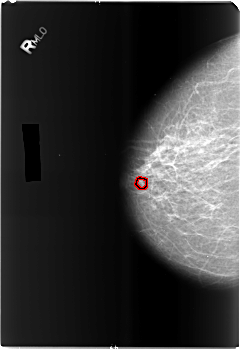

B_3489_1.RIGHT_MLO

RIGHT_MLO LINES 5896 PIXELS_PER_LINE 4080 BITS_PER_PIXEL 12 RESOLUTION 50 OVERLAY

FILE: B_3489_1.RIGHT_MLO.OVERLAY

TOTAL_ABNORMALITIES 1

ABNORMALITY 1

LESION_TYPE CALCIFICATION TYPE ROUND_AND_REGULAR-PLEOMORPHIC DISTRIBUTION CLUSTERED

ASSESSMENT 4

SUBTLETY 3

PATHOLOGY BENIGN

TOTAL_OUTLINES 1

BOUNDARY